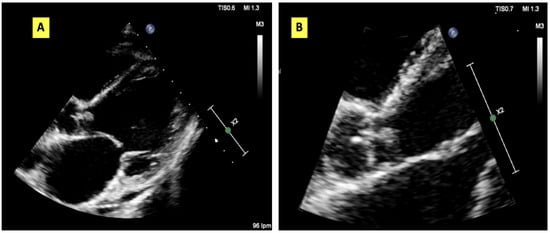

Background: Aspergillus endocarditis is a rare but life-threatening form of infective endocarditis that typically occurs in patients with a history of cardiac surgery, prosthetic valve implantation, or profound immunosuppression. Native valve involvement in non-traditional hosts remains exceptionally rare and is diagnostically challenging. [...] Read more.

Background: Aspergillus endocarditis is a rare but life-threatening form of infective endocarditis that typically occurs in patients with a history of cardiac surgery, prosthetic valve implantation, or profound immunosuppression. Native valve involvement in non-traditional hosts remains exceptionally rare and is diagnostically challenging. Case presentation: We describe a 56-year-old woman with CREST syndrome and advanced liver disease awaiting transplantation who developed native aortic valve endocarditis. Blood cultures and serum biomarkers (galactomannan and β-d-glucan) were also negative. Transthoracic echocardiography revealed vegetation on the aortic valve. Valve replacement was performed, and Aspergillus fumigatus was isolated from two valve cultures. Liposomal amphotericin B was initiated; however, the patient died of multiorgan failure two weeks later. Systematic review: To contextualise this case, we conducted a systematic review of the literature following the PRISMA guidelines. We included microbiologically confirmed cases of native valve Aspergillus endocarditis based on valve or embolic tissue analysis. Forty-three studies met the inclusion criteria, comprising 45 patients in total. Data were independently extracted by two reviewers and narratively synthesised due to clinical heterogeneity. Conclusions: This case illustrates the diagnostic and therapeutic challenges of native-valve Aspergillus endocarditis in patients without classical risk factors for the disease. Early imaging and a high index of suspicion are crucial for diagnosis. Combined surgical and antifungal therapy remains the cornerstone of management, although the mortality rate remains high. Full article